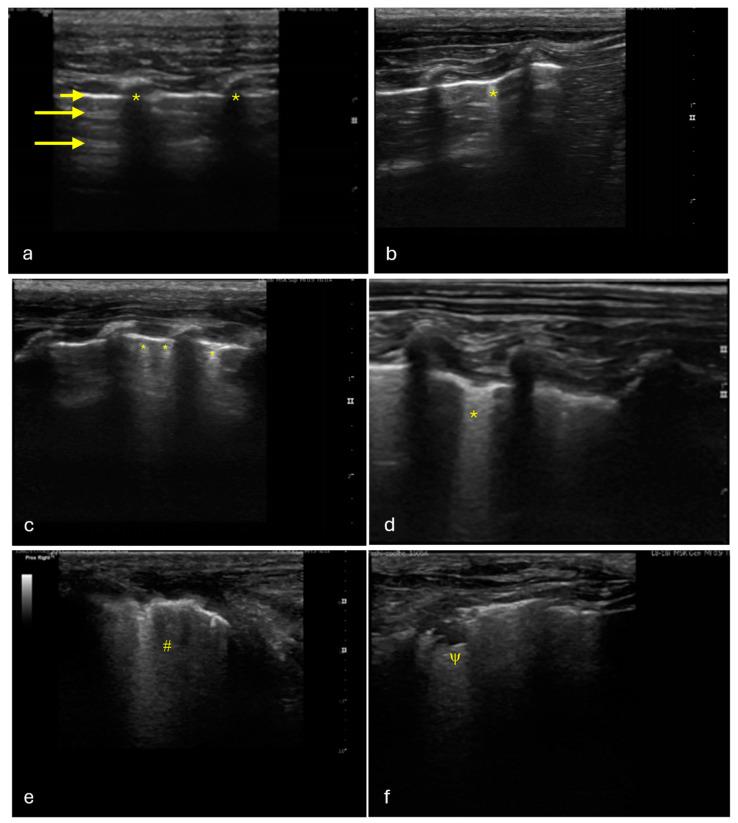

Rabbits are commonly affected by subclinical lung diseases. Computed tomography (CT) is the gold standard for diagnosing rabbit lung diseases but is not widely available and requires anesthesia, delaying diagnosis. Lung ultrasound (LUS) has emerged as a radiation-free, bedside diagnostic tool in human and veterinary medicine, though its use in rabbit medicine is not routine. This study aimed to evaluate LUS for detecting subclinical lung lesions in rabbits. Thirty healthy, five-month-old male New Zealand white rabbits underwent lung ultrasound, exploring four regions in each hemithorax, followed by thoracic CT under sedation with midazolam and butorphanol. The ultrasound images were scored as positive or negative, and the CT exams were assessed for aeration using threshold masks. The results showed that 63% of rabbits had one or more affected regions in the ultrasound images, and 19% of the regions were positive. CT identified 54% of the regions as positive for poorly aerated tissue, with 26/30 rabbits showing at least one positive region. The sensitivity and specificity of LUS were 33.33% and 93.48%, respectively, with an accuracy of 67.92% for detecting subclinical lesions. While LUS demonstrated a high specificity, its sensitivity was low compared to CT, highlighting the need for further refinement in its use for rabbit respiratory disease diagnosis.

兔子通常会受到亚临床肺部疾病的影响。计算机断层扫描(CT)是诊断兔子肺部疾病的金标准,但该设备并不普及,且需要麻醉,这会延误诊断。肺部超声(LUS)已成为人类和兽医学中一种无辐射的床边诊断工具,不过其在兔医学中的应用并不常规。本研究旨在评估LUS检测兔子亚临床肺部病变的能力。30只健康的5个月大雄性新西兰白兔接受了肺部超声检查,对每个半胸的四个区域进行探测,随后在咪达唑仑和布托啡诺镇静下进行胸部CT检查。超声图像被评为阳性或阴性,CT检查则使用阈值掩码评估通气情况。结果显示,63%的兔子在超声图像中有一个或多个受影响区域,其中19%的区域为阳性。CT识别出54%的区域为通气不良组织阳性,30只兔子中有26只显示至少一个阳性区域。LUS检测亚临床病变的敏感性和特异性分别为33.33%和93.48%,准确率为67.92%。虽然LUS显示出高特异性,但其敏感性与CT相比很低,这突出表明在将其用于兔呼吸道疾病诊断方面需要进一步改进。